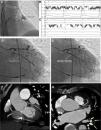

Because the LAA has a very thin wall and may be prone to perforation, LAA electrical isolation (LAAEI) is currently performed by delivering radiofrequency (RF) energy at the level of the LAA ostium, which is considerably thicker. Panikker demonstrated in cadaveric hearts that the thickest LAA ostial areas requiring longer RF ablation are the anterior (2.5±0.8 mm [range, 1.4-4.0 mm]) and superior (2.4±1.2 mm [range, 1.1-4.8 mm]) edges (Figure 3).12 LAAEI is usually guided by intracardiac echocardiography and 3-dimensional mapping systems using a circular mapping catheter. To obtain electrical isolation in this structure, up to 30 minutes of high power RF ablation are required in some cases. The RF settings during LAAEI include power up to 43 Watts, while maintaining a catheter tip temperature of 42°C for a maximum of 60 seconds per ablation site (Figure 4).

Sites of acute LAA reconnection and regional variation in LAA ostial thickness. (A) Location of acute LAA reconnection sites superimposed on right anterior oblique (35°) fluoroscopic view of the LA with contrast opacified LAA. All of the reconnection sites are located at the base of the LAA. The location of each reconnection is marked with a circle on the segment of LAA involved. (B) Gross view of non-ablated LAA, LSPV, and mitral valve. The LAA walls were cut longitudinally along the red and blue lines, and the regional LAA wall thickness was measured. Asterisks indicate significantly thicker ostial tissue at superior and anterior LAA margins compared with inferior and posterior margins (p=0.02). Sections through anterior and posterior walls (C) and superior and inferior walls (D). Note the close proximity of the left circumflex coronary artery to the anterior wall of the LAA. Adapted from Circ Arrhythm Electrophysiol. 2016;9:e003710.

Top: Electroanatomic voltage map of a 79-year-old patient with ischemic cardiomyopathy who underwent CABG, cox-MAZE procedure and LAA ligation in 2011 for persistent AF. Patient presented to CCU with decompensated heart failure and AF with rapid ventricular response. Voltage map revealed severe right and left atrial scarring. Pre (left) and post (right) LAAEI. Note RF ablation lesions delivered at the ostium of the LAA. Middle: PentaRay catheter is in the LAA while delivering RF energy. Note that AF terminates into normal sinus rhythm. Bottom: PentaRay catheter is in the LAA showing no signals demonstrating LAAEI.